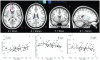

Methodology/principal findings: We tested this hypothesis in a group of healthy adolescents, age 12-18 (N = 91), who underwent diffusion tensor imaging (DTI) to delineate cortical white matter tracts. As a measure of real-world risk taking, participants completed the Adolescent Risk Questionnaire (ARQ) which measures engagement in dangerous activities. After adjusting for age-related changes in both DTI and ARQ, engagement in dangerous behaviors was found to be positively correlated with fractional anisotropy and negatively correlated with transverse diffusivity in frontal white matter tracts, indicative of increased myelination and/or density of fibers (ages 14-18, N = 60).

Conclusions/significance: The direction of correlation suggests that rather than having immature cortices, adolescents who engage in dangerous activities have frontal white matter tracts that are more adult in form than their more conservative peers.